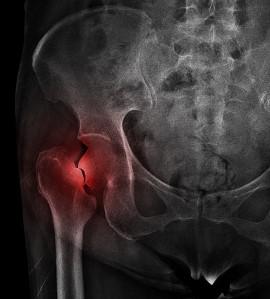

Tudnunk kell azonban, hogy nem minden törés csontritkulás következménye. Ezzel a kórképpel összefüggésbe hozható törések jellegzetes helyeken jönnek létre, mint például a combnyak, a csukló területe, vagy a csigolyatestek.

Röntgenképen ábrázolt jobb oldali combnyaktörés